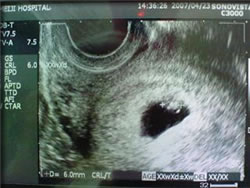

思えば、去年の昨日はあまりにも具合が悪い日が続いたため、また諸々の症状から、当時はまだただの彼氏だった チャンに言われて、午後から仕事を休み、産婦人科を受診したのでありました。 よく晴れた暖かい日だったにもかかわらず、一人ダウンコートを着ており、看護婦さんからは「妊婦さんはこの時期寒気がするんだよね」と言われたこと、超音波検査で小さな生き物がピョコピョコ動いていたこと、出張生活を送っていたチャンにメールしたこと、当時のアパートのお隣さんのこいのぼりに向かって、無事に産まれますようにと祈ったこと、等々思い出します。 当時6mmだった息子様は、先日4ヶ月健診を受け、身長61.8cm、体重6370gと小さめながらも順調に育っております。 巨大になったもんだわ。